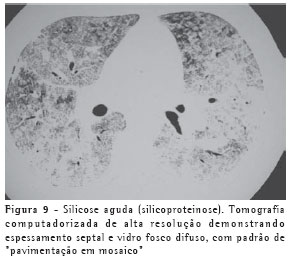

As duas outras formas de silicose são a acelerada, causada pela inalação de grandes quantidades de sílica, com evolução mais rápida que a crônica, e a silicose aguda, também conhecida como silicoproteinose, decorrente da inalação maciça de sílica por períodos muito curtos. Nesta forma da silicose, a radiografia e a TCAR (Figura 9) demonstram opacidades pulmonares difusas, por vezes associadas a espessamento de septos interlobulares e vidro fosco (padrão de "pavimentação em mosaico").(5)